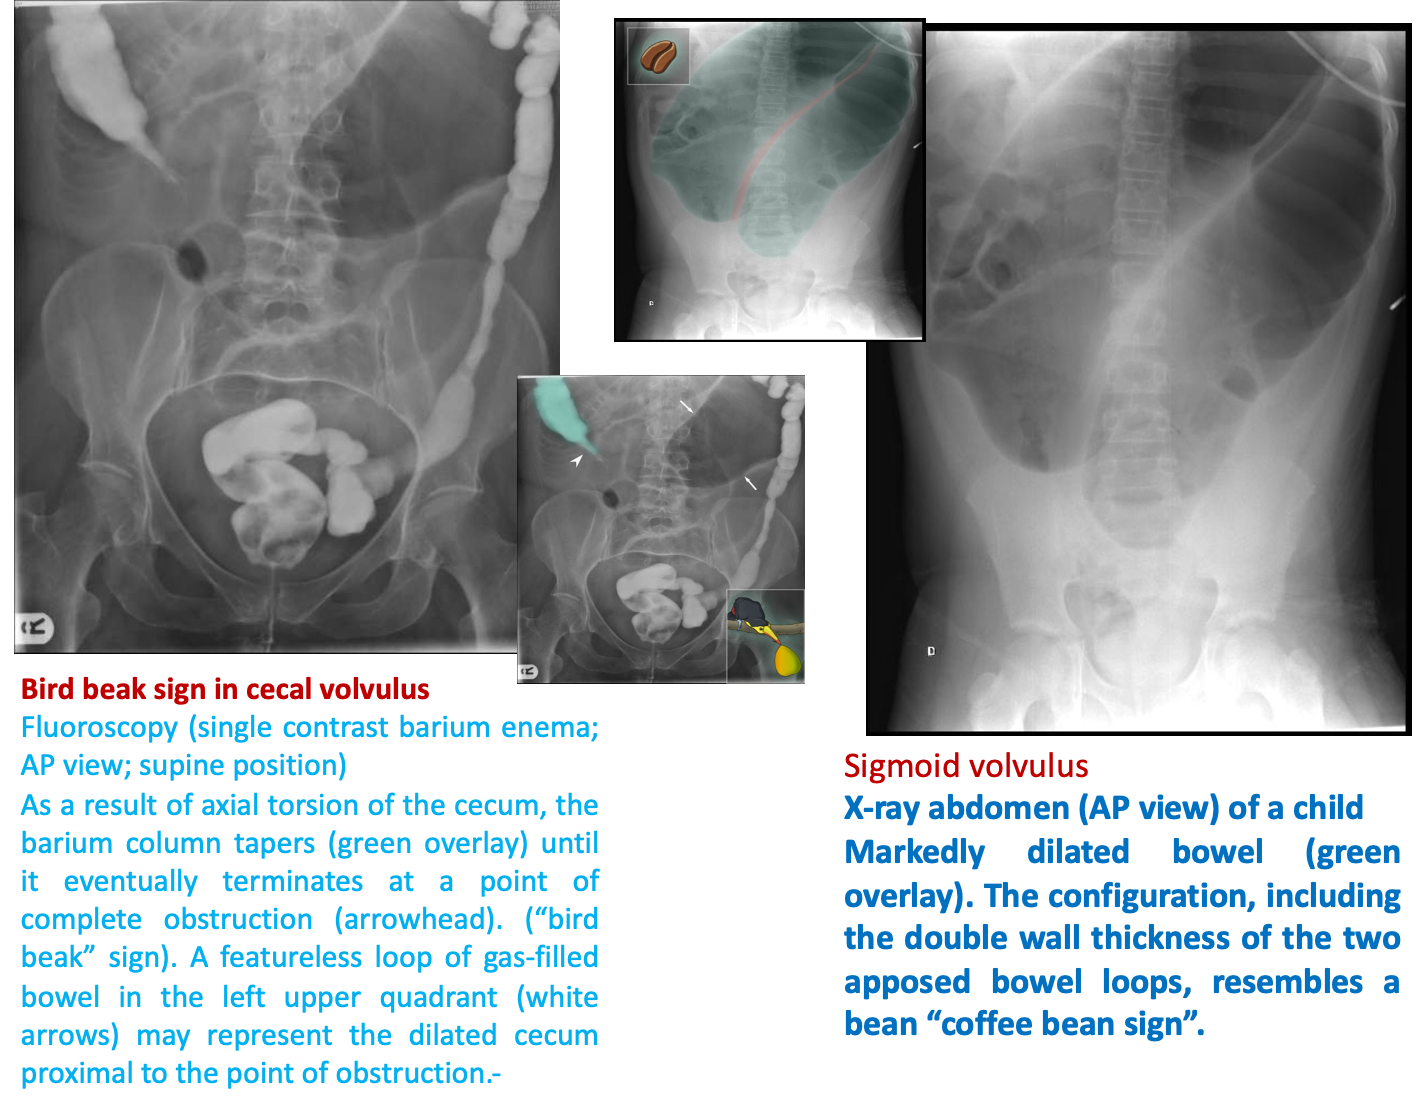

Sigmoid volvulus: coffee bean sign: dilated loop of sigmoid colon with absent haustrae; Absence of air in the rectum

Cecal volvulus: dilated loop of cecum with maintained haustrae.; The colon distal to the obstruction does not dilate

Barium enema :

bird beak sign (tapering of the dye column at the site of the twist)

- Sigmoid volvulus: Bird’s beak sign at the sigmoid; dye does not enter the sigmoid colon.

- Cecal volvulus: Bird’s beak sign at the cecum; dye does not enter the small bowel